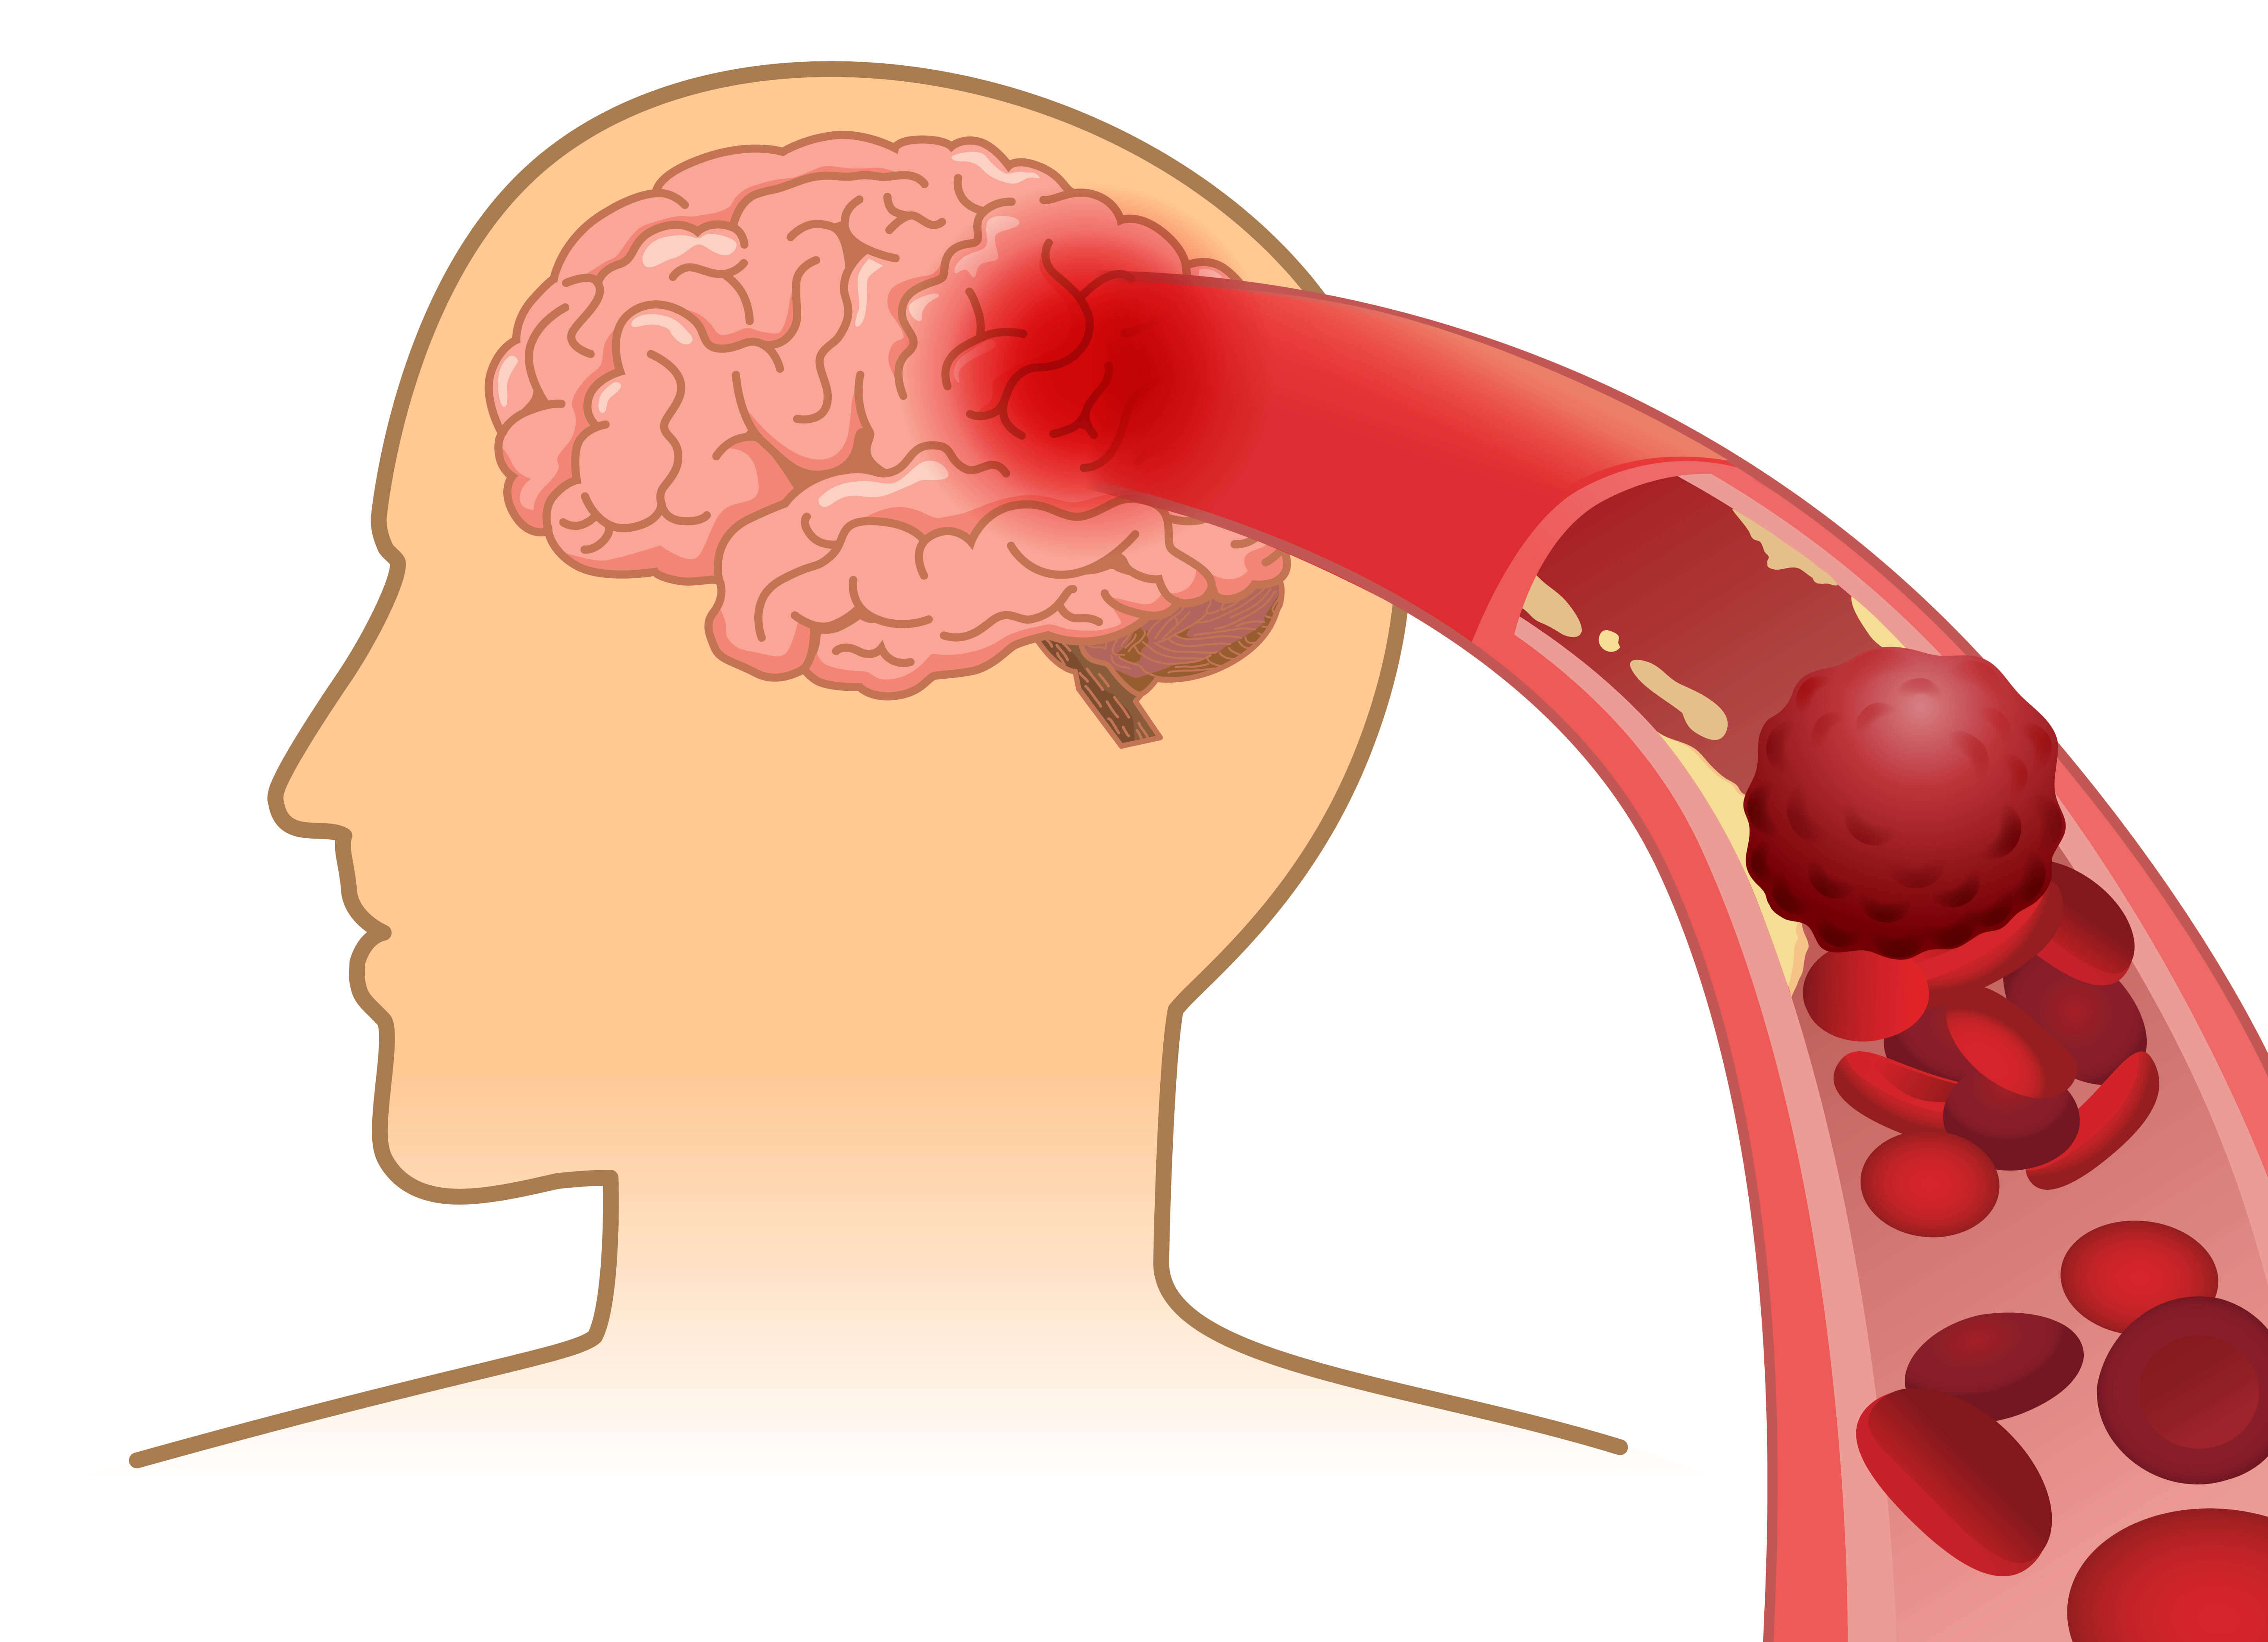

7. Bra för blodet

Ägg innehåller folat vilket är en typ B-vitamin som behövs för att bilda nya röda blodkroppar.

9. Minskad risk för hjärtproblem

Det finns ett samband mellan äggrik kost och minskad risk för hjärt- och kärlsjukdomar och cancer, skriver Må Bra.